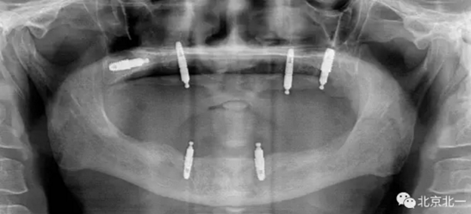

圖二:覆蓋義齒

2.png